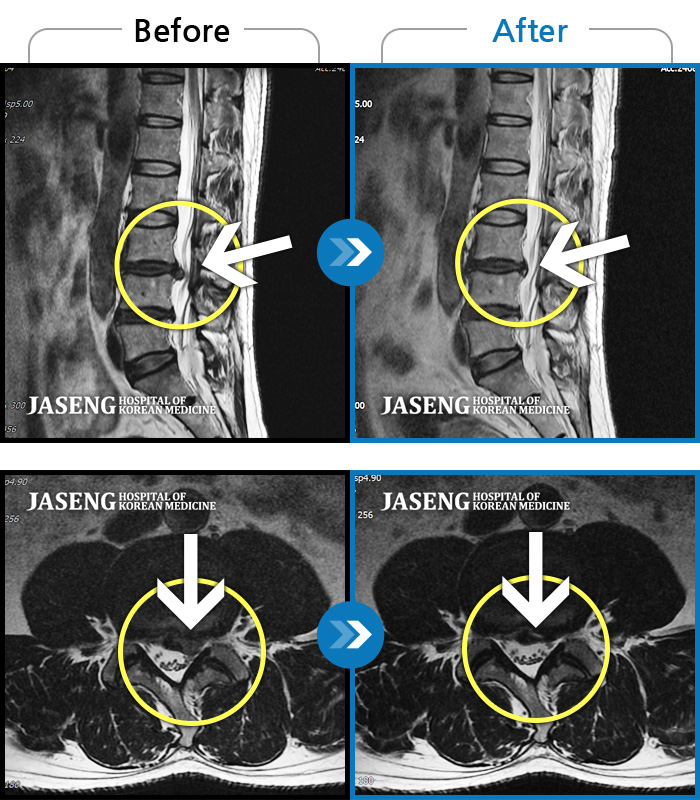

이번에 목 디스크가 타 병원 수술 소견까지 나오고 밤에 잠을 못잘정도로 통증이 심해서 고민 중 역시 김유진 원장님이 최고의 선택이며 최고의 선택임을 믿고 입원 치료 중입니다

수술을 해야 하는 상황이었는데 자생 한방 병원의 김유진 원장님 덕분에 현재 수술없이 잘 치료를 받고 있습니다.

처음에 수술없이 완쾌할수 있을까 걱정을 많이 했지만 지금은 완쾌할수 있을거랑 희망을 가지고 통원치료를 받고 있습니다.